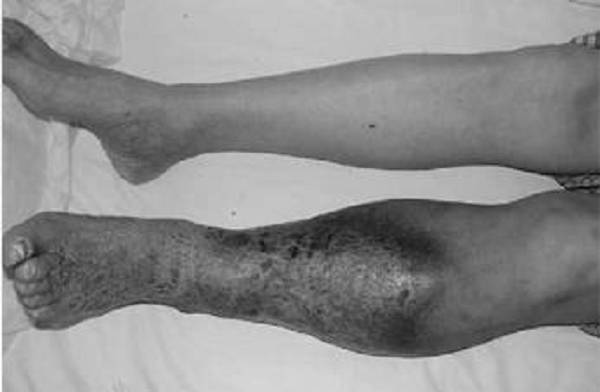

肺栓塞是静脉血栓最严重的临床表现,是人类死亡的第三大原因。肺栓塞可无症状,部分患者首发表现为猝死,其中突发致死性肺栓塞占34%,死前未能确诊的占59%,仅7%的早期死亡病例在死前确诊。深静脉血栓急性期会导致股青肿、股白肿,严重时截肢风险。深静脉血栓后综合征是一种慢性、进展性疾病,一般在深静脉血栓发病后6个月做出诊断。患者可表现为下肢血液循环障碍、静脉性跛行、皮肤难愈性溃疡甚至丧失劳动力 。

▲ 下肢深静脉血栓综合征合并溃疡